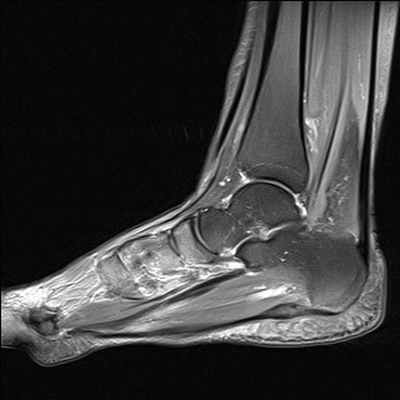

приходится до 25% от общего количества травм опорно-двигательного аппарата и 40-60% от числа повреждений нижней конечности. Диагностировать патологии области сочленения ноги и ступни можно с помощью рентгена, КТ и МРТ. Данные рентгенографии и компьютерной томографии в большей степени сфокусированы на визуализации костных тканей. Магнитно-резонансная томография явилась методом комплексной оценки повреждений голеностопного сустава и стопы. Её чувствительность в диагностике травматических повреждений и дегенеративных патологии в среднем составляет 98%, специфичность - 89%, точность - 94%. МРТ голеностопа позволяет получить четкие послойные снимки костей голеностопного сустава, хрящей, связочного аппарата, сухожилий, сосудов и окружающих их мягких тканей.

Что видно на МРТ голеностопа?

В ходе томографии голеностопного сустава оцениваются следующие анатомические аспекты:

- Взаимоотношения суставных поверхностей в голеностопном суставе и выпот стопы.

- Состояние подтаранного сустава.

- Проверяется, что медиальная и латеральная лодыжки не повреждены. Сухожилия задней и передней большеберцовых мышц, длинного сгибателя пальцев, длинной и короткой малоберцовых мышц не изменены или воспалены.

- Нет ли деформации и воспаления по ходу сухожилия задней б/берцовой мышцы.

- Дельтовидная связка носит целостный характер.

- Перонеальный удерживатель сухожилий не изменен.

- Передняя и задняя межберцовые связки не повреждены, щель межберцового синдесмоза равномерна и не расширена.

- Передняя малоберцово-таранная связка не определяется за счет отрыва от наружной лодыжки.

- Задняя малоберцово-таранная связка утолщена и разволокнена за счет растяжения и определяется на всем протяжении.

- Задний край таранной кости не деформирован.

- Пяточное (Ахиллово) сухожилие без патологических особенностей. Подошвенная фасция равномерно утолщена, а тарзальный канал не изменен.

- Собственно голеностопный и подтаранный суставы не деформированы.

- Мышцы не деформированы и однородны по интенсивности МР-сигнала.